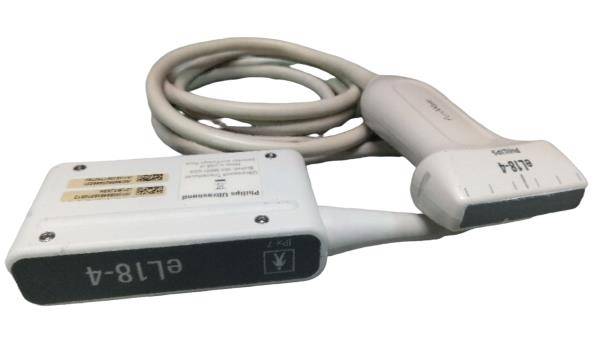

Probe Type

80 elements

Frequency

Convex array 2-5MHZ / Linear array 5-10MHZ